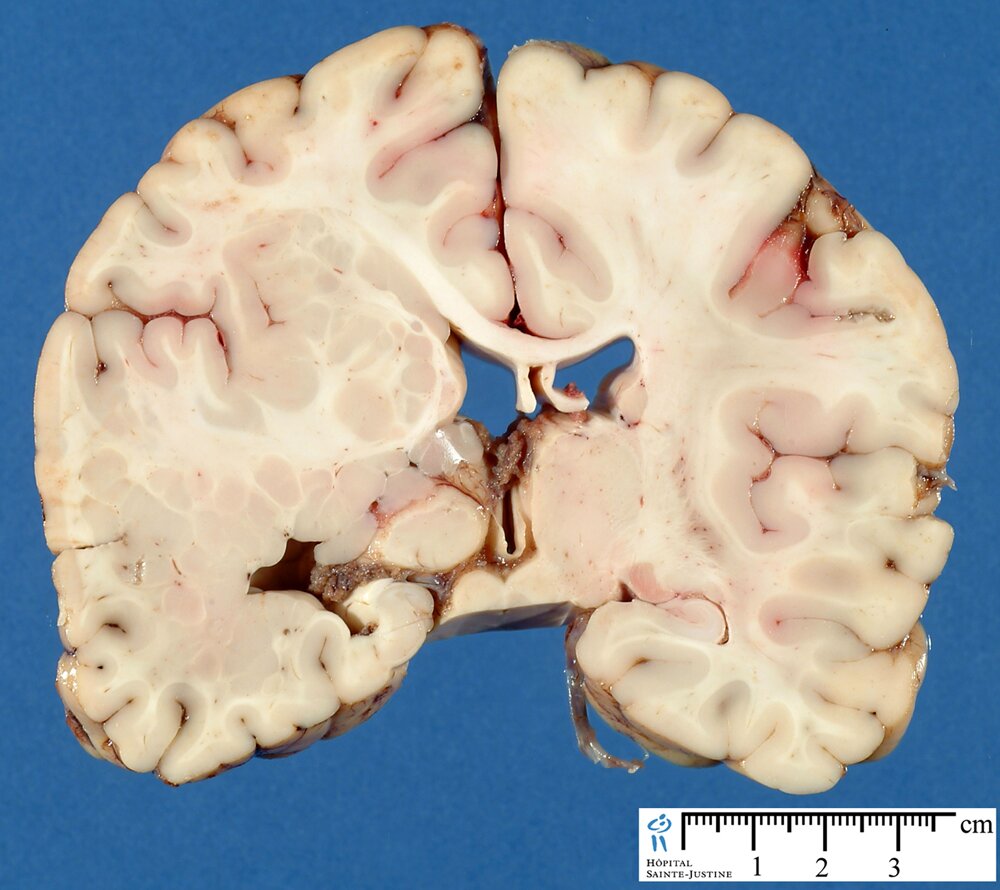

Periventricular heterotopia (PH) is characterized by neuronal nodules along the lateral ventricles.